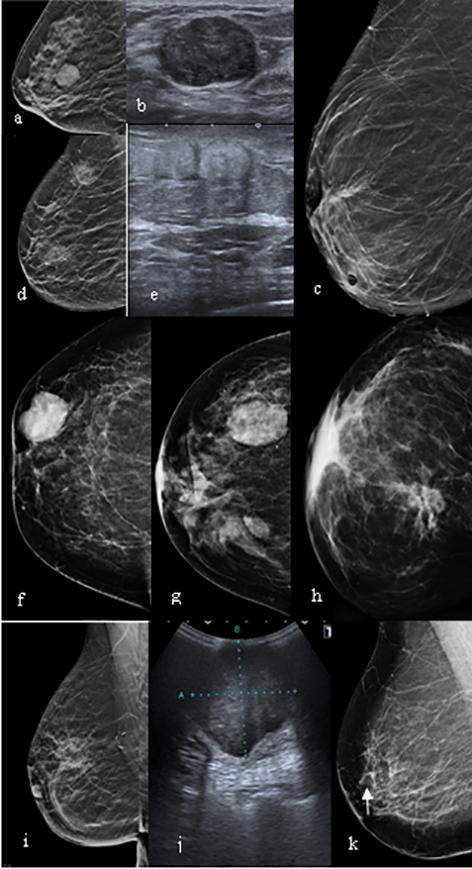

At our institution, all patients with rib fractures were admitted to a trauma ICU ward and offered the standard of care as per protocol of the unit, including intravenous analgesia; oxygen, nebulised bronchodilators as needed, mechanical ventilation when indicated, management of associated injuries and active physiotherapy. A computed tomography scan (CT) of the chest was obtained and three-dimensional (3-D) volume reconstructions performed to evaluate the thoracic skeleton and assess indication for surgery.

The surgical procedure to fix the ribs was performed using a muscle sparing thoracic incision (Figure 1). The ribs were stabilised using titanium plates and screws (RibFix BluTM, Zimmer Biomet, Jacksonville, USA); an effort was always made to provide stability for all accessible fractures.

Figure 1: A typical example of multiple rib fractures and three plated fractures

Numeric visual pain scale (VAS) assessments were administered to all conscious patients; overall the median VAS pain on admission for non-ventilated patients was 8 points (range 6–10), operated patients who were not ventilated demonstrated significant immediate postoperative reduction of the pain scales to a median of 2 out of 10 (range 1–4) (Figure 2).

IV: Time to return to normal activities Weeks Surgery Best medical 3 or less 8 4 to 6 3 10 7 or more 3 11 Average 5.3 9.3 Median (Range) 3 (2–18)* 7 (4–36) (*) Student’s t-test p = 0.003 p = 0.04* 12 10 8 6 4 2 0 Pain VAS Medical Surgical Post op

2:

(VAS)

Case by case pain VAS

Figure

Pain: numeric visual analogue scales